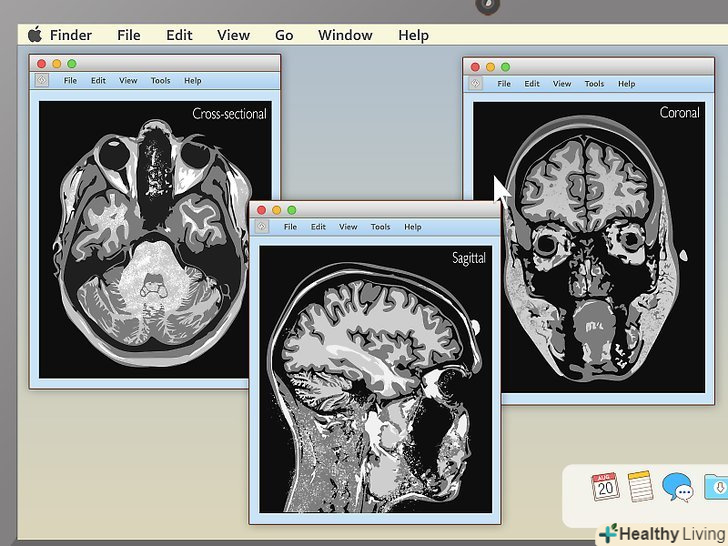

Дізнайтеся, якими способами можна переглядати знімки.коли МРТ завантажиться, якщо вам пощастить, ви відразу зрозумієте,що перед вами. Однак дуже часто на знімку буде лише абсолютно незрозуміла суміш з чорного, білого і сірого. Розуміння того, як робиться МРТ, допоможе вам прочитати знімок. Є три площини, в яких переглядають органи при МРТ:[5]- Саггитальная. Зазвичай такі знімки найпростіше інтерпретувати. Саггітальний перегляд-Це перегляд органів або тканин збоку або в профіль. Зображення являє собою вертикальний розріз у двосторонній симетрії.

- Корональна. Це фронтальна площина. Ви розглядаєте органи людини, яка немов стоїть обличчям до камери.

- Поперечна. Як правило, з цією площиною працювати непрофесіоналам найскладніше. Ця площина немов нарізає тіло на дрібні горизонтальні смужки.